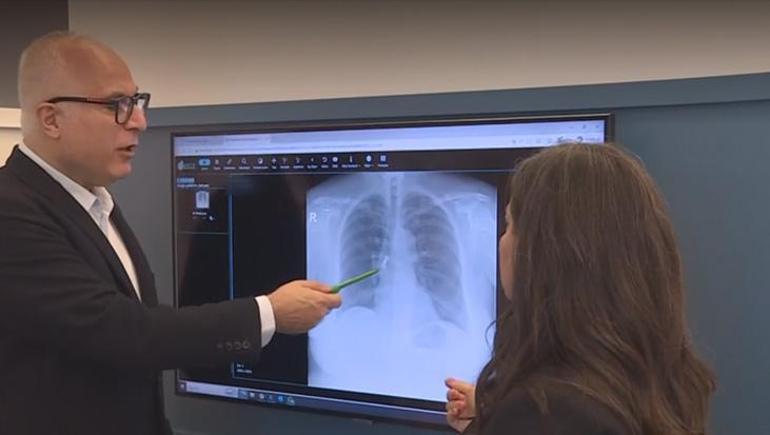

Kadın hastanın üst arka tarafta bulunan üçlü kaplama dişi akciğerine kaçtı. Sabah uyandığında dişlerinin yerinde olmadığını gören hasta acilen hastaneye başvurdu. Çekilen röntgen filminde dişlerin akciğerde olduğu görüldü. Hasta şanslıydı, çünkü soluk borusu tamamen tıkanabilirdi. Akciğerdeki diş bronkoskopi yöntemiyle çıkarıldı.

Göğüs Hastalıkları Uzmanı Prof. Dr. Levent Alpay, akciğer filminde üç dişten oluşan kaplama köprüsünün aspire edildiğini fark ettiklerini ve hastayı hemen yatırdıklarını söyledi. Sabah uyandığında dişlerinin yerinde olmadığını gören hastanın, dişleri yutmuş olabileceğini düşündüğünü belirten Alpay, bu tür durumlarda genellikle mideye kaçma ihtimalinin daha yüksek olduğunu vurguladı.

“Çekilen akciğer filminde kaplama dişin üç dişten oluşan kısmının aspire edildiğini görerek hastamızı hemen yatırdık. Sabah uyandığında dişlerinin ağzında olmadığını gören hasta, “Acaba yuttum mu?” diye düşündü. Genelde bu tür durumlarda yutma söz konusu olur.